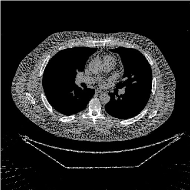

This paper was inspired by a simple observation related to our recent study [34]: for the penalized weighted-least squares (PWLS) reconstruction method using prior with a learned ST (PWLS-ST-) [34], the sparsification error histograms match a Laplace distribution over the iterations; see Fig. 1. The question then arises, “Does the learned prior experience model mismatch in testing stage?” To answer this question, we aim to investigate learned STs for regularization. This paper

The term denotes a -based sparsification error [3, 4, 5]. We expect to be more robust to sparsity model mismatch than the -based sparsification error used in [34, 36]. Fig. 1 shows histograms of sparsification error at different outer iterations of the PWLS-ST- method. Over the iterations, the sparsification error histograms appear more like a Laplace distribution than a Gaussian distribution. This observation suggests that the proposed prior model is more suitable than the prior model for PWLS-ST-based reconstruction. Section III-B1 shows that the proposed -based sparsification error term, , improves the accuracy of reconstruction compared to the prior model in [34, 36].